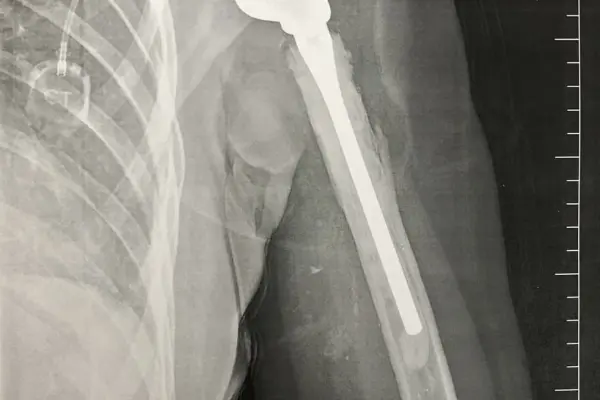

V říjnu 2020 se na CT objevila další metastáza, hned vedle té z předchozího roku. Podstoupila jsem další resekci plíce. A pak se držela. Začala jsem znovu brigádničit v kavárně. Bavilo mě to. Nové tváře, pravidelní návštěvníci, se kterými už prohodíš pár slov, dortíčky a kafíčka. A doma na mě čekala Enie s kterou jsme nadále objevovaly všechno, co šlo. S Jirkou jsme se mezitím přestěhovali do většího bytu. Bylo nám fajn. Měla jsem pocit, že už jsem snad konečně z nejhoršího venku. A věřili jsme tomu všichni. V říjnu 2022 mi dali do kupy rameno. Dostala jsem totální endoprotézu, jak bylo v plánu od úplného začátku. To mi pár týdnů po skončení rehabilitací vypadlo, takže na nahození jsem musela zase pod narkózu, ale jak už jsem jednou psala, byly to pro mě „jen“ kosmetické operace.